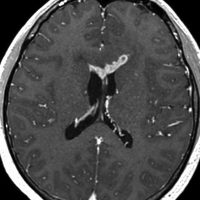

ICEを3コース行なって腫瘍は完全消失して,前頭葉浮腫も消えました。その後に,全脳照射 25.2Gy/14分割を加えました。無症状で復職することができました。